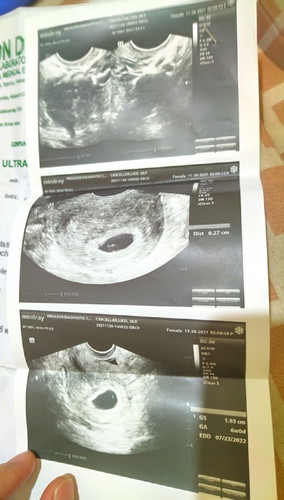

Trans V ultrasound

Hello po ask ko lang po kung ano pong ibig sabihin netong trans v ko? Bagamat na explain po sakin di ko pa din po masyadong naiintindihin. May same case po ba sakin dito? Pinababalik ako ukit after 3 weeks para i trans v ulit ako. Wala po bang baby sa ultrasound ko may nabanggit pa sakin about sa bugok daw pero wag naman daw sana kaya nag second opinion po? Thank you sa sasagot 😒#pleasehelp #pregnancy